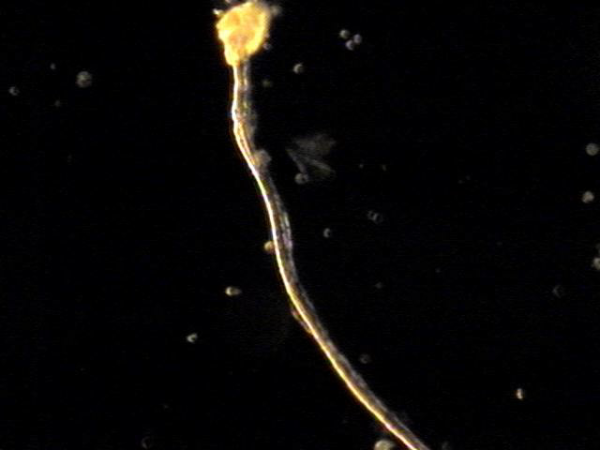

주 2회 전립선과 전립선관, 사정관 입구와 사정관과 정낭 그리고 정관등의 표적 치료후 치료된 현미경학적 자료입니다.

This is a microscopic image taken after twice-weekly targeted treatment of the prostate, prostatic ducts, ejaculatory ducts, seminal vesicles, and vas deferens.

It shows tissue fragments and inflammatory materials that had blocked these passages. Through treatment, these obstructive materials were cleared, helping to improve circulation and function.

This process may support better semen flow and reduce symptoms related to blockage or inflammation.

전립선과 정관 그리고 사정관과 정낭등의 표적 치료후 현미경학적 사진과 윗쪽은 정관에 막혀 있던 치료된 사진과 아랫쪽은 전립선관의 치료된 사진.

Here we see two microscopic images after targeted treatment of the prostate, seminal vesicles, ejaculatory ducts, and vas deferens etc.

- The image on the above appears to show material that was once blocking the vas deferens, now cleared after treatment.

- The image on the below seems to show a treated prostatic duct, where the obstruction has also been resolved.

These findings suggest that the therapy helped improve the passageways involved in semen transport.